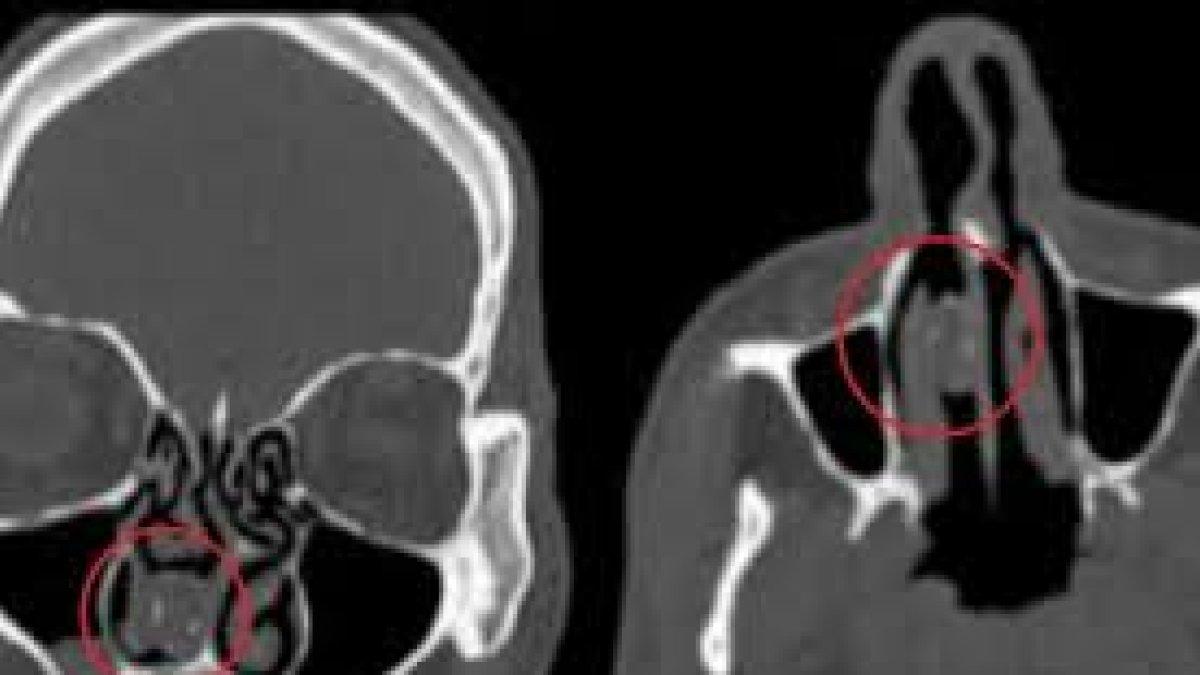

Los análisis del escáner revelaron que dentro había una masa gris firme y por ello los médicos decidieron realizar una endoscopía con anestesia general para sacarla. Al extraerla descubrieron que era una “cápsula de goma que contenía vegetales en descomposición”, dijo el médico tratante.

El globo de 1,9 centímetros de largo, se transformó en un “rinolito” que quiere decir “piedra en la nariz”.